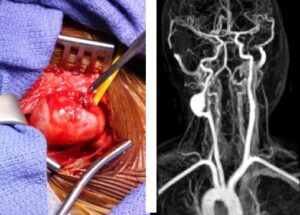

Первые признаки аневризмы сонной артерии (сосудов шеи): лечение и прогноз выживаемости

Аневризма сонной артерии — это аномальное расширение или выпуклость стенки сосуда с одной или обеих сторон, которое развивается латентным образом. Общие сведения Анатомические аномалии сосудов представляют огромную угрозу для жизни и здоровья пациента. Однако органические аномалии редко становятся ясно видимыми, пока не станет слишком поздно. Клиническая картина недостаточно конкретна, а иногда и вовсе отсутствует. Второй …